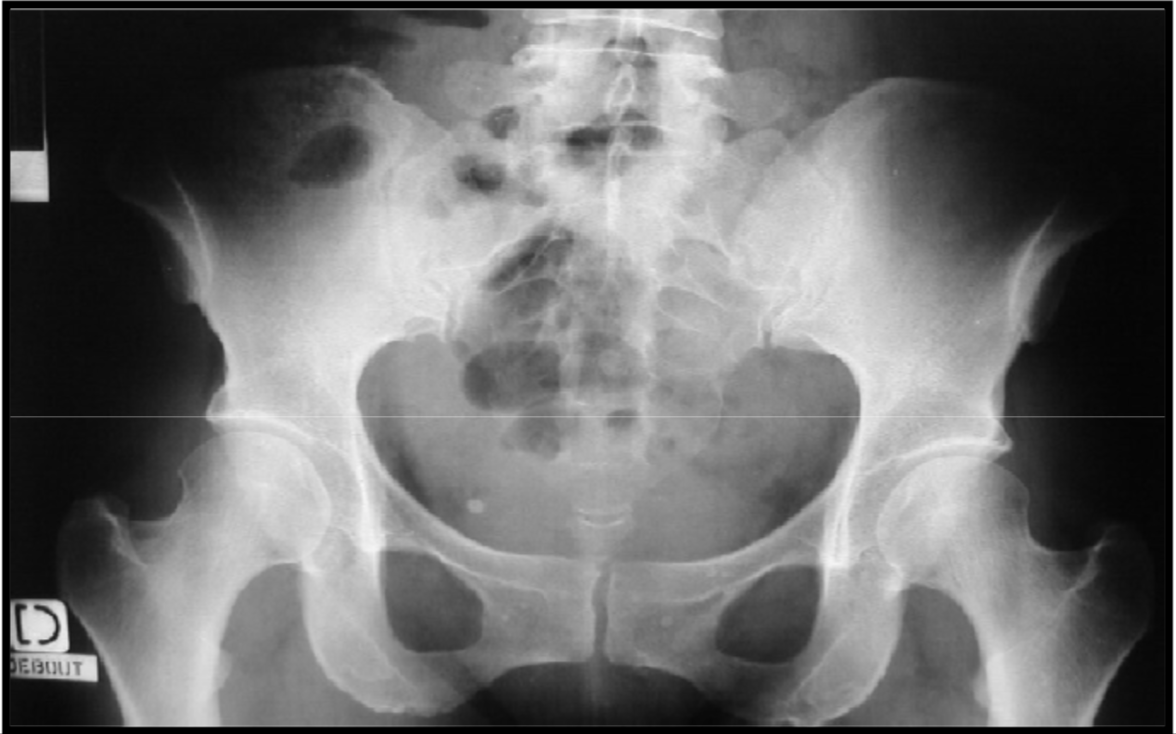

Phlebolith’s (calcified venous thrombi)

Bone islands

variation anat

à comparer voir si ce n’est pas une métastase ostéoblastique

Osteoblastic metastases